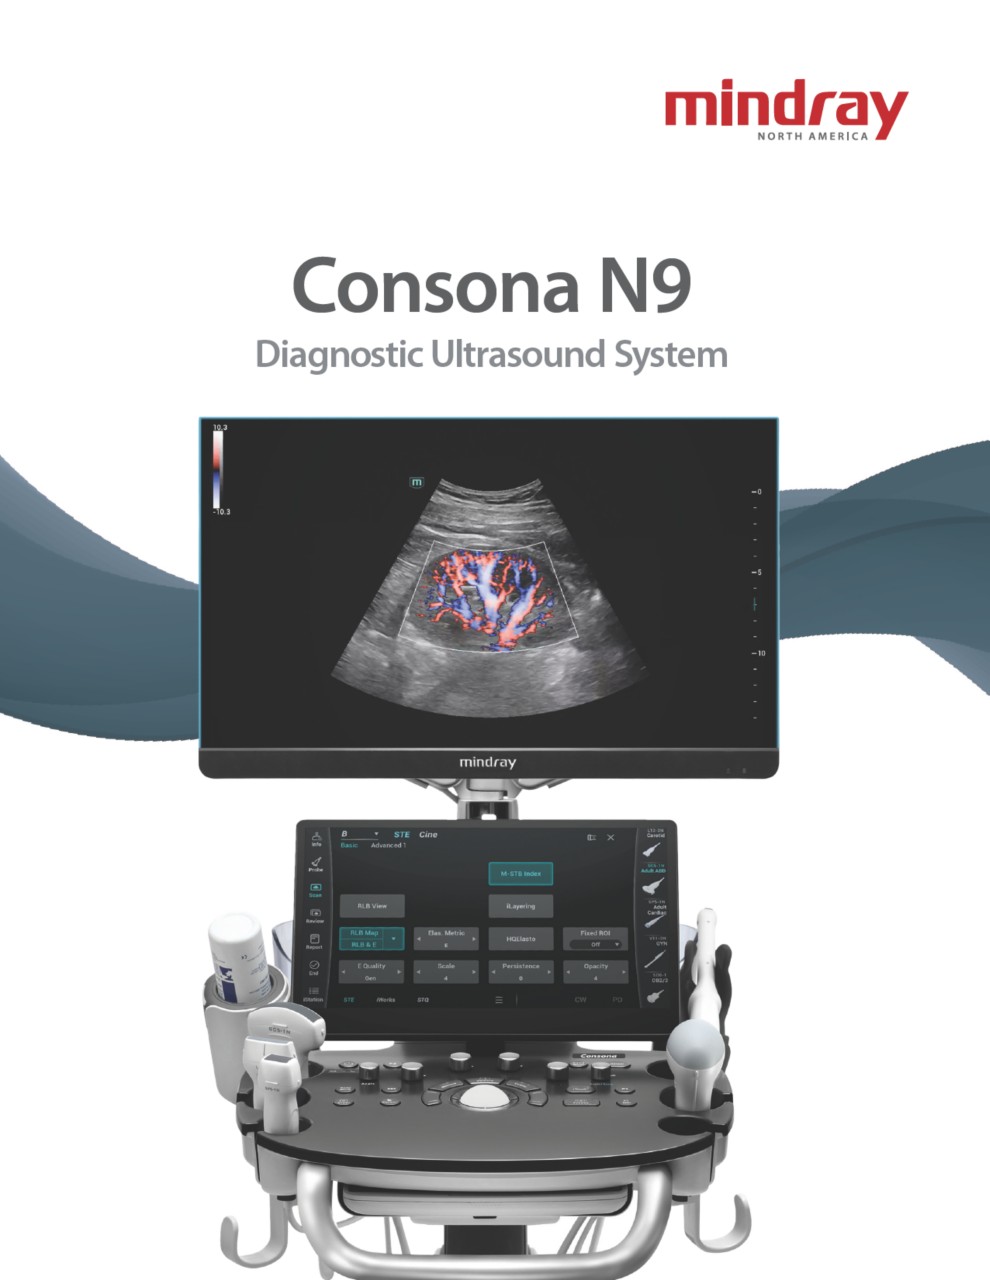

Consona N9

Ultrasound Machine

Women's Health | Radiology | Cardiovascular Imaging